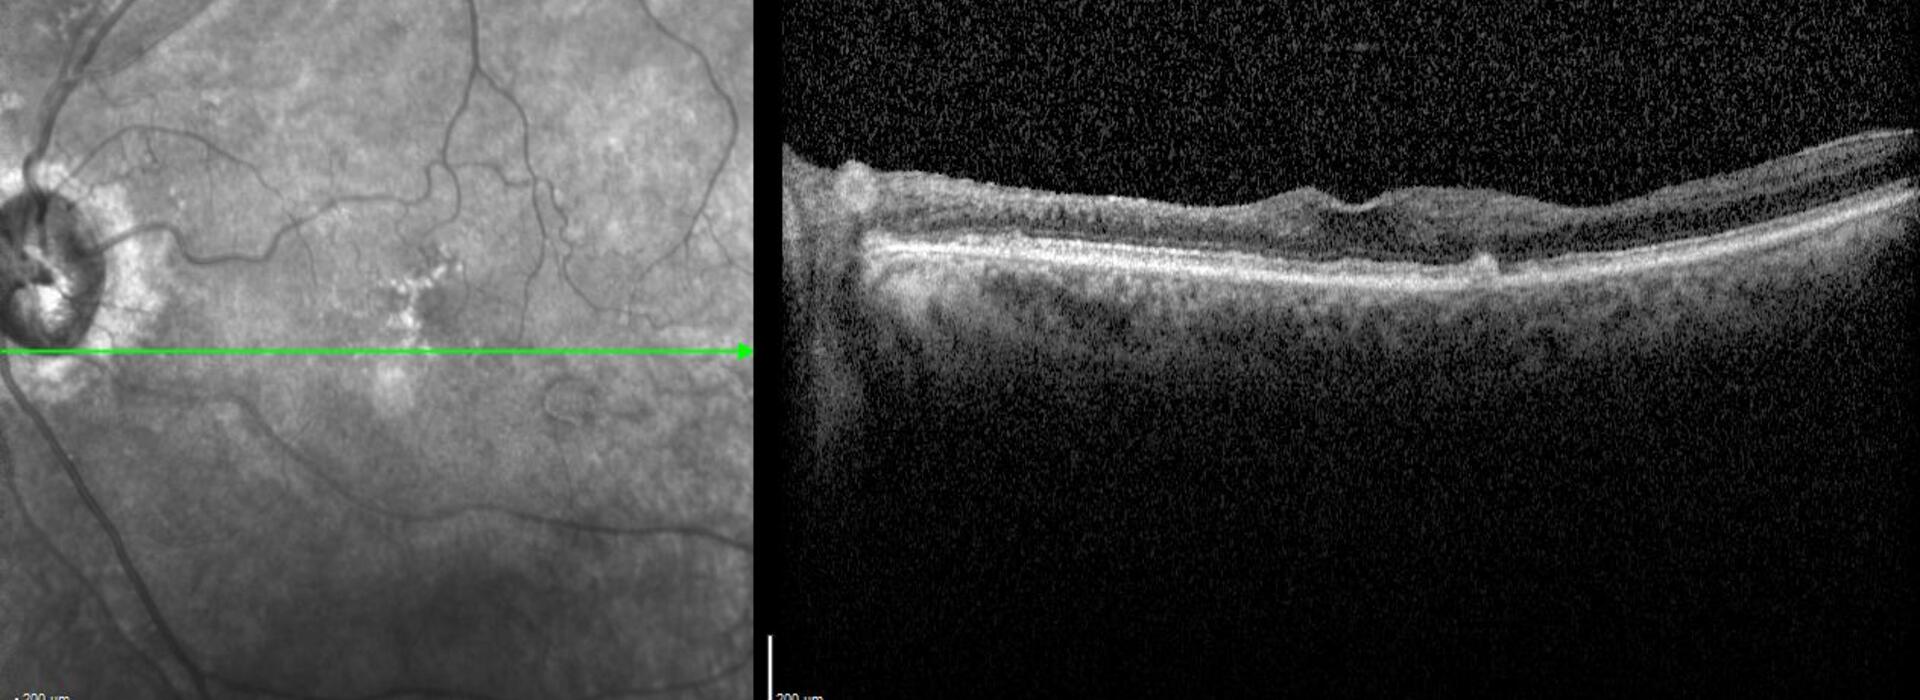

ISQUEMIA RETINIANA DEL PLEXO SUPERFICIAL Y PROFUNDO

El Dr Javier Montero resume los signos directos e indirectos en la tomografía de coherencia óptica estructural y angiográfica para identificar los cambios derivados de la isquemia retiniana